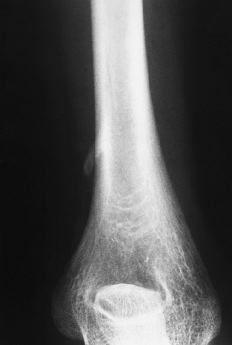

En el estudio radiológico se apreció una prominencia ósea situada en la cara anteromedial del húmero, a unos 5 cm por encima de la epitróclea, cuyo tamaño era de unos 2 cm de largo, de base ancha y forma alargada dirigida en dirección inferior y anterior (Fig. 1). Ante el diagnóstico de apófisis supraepitroclear, y debido a la clínica neurovascular que presentaba la paciente, se optó por el tratamiento quirúrgico.

ABFigura 1. A: Rx AP. Se aprecia la apófisis supraepitroclear en dirección craneocaudal y hacia medial. B: Rx lateral.